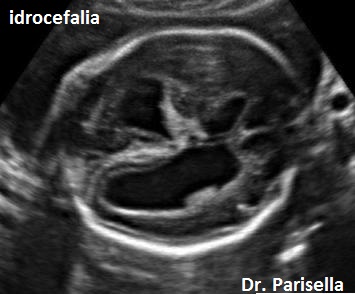

E' una displasia scheletrica caratterizzata da nanismo rizomelico con incurvamento del femore e della tibia. Si associano dismorfismo facciale (con micrognazia e palatoschisi), ipoplasia toracica  con coste corte (di solito sono presenti 11 paia di coste), ambiguità dei genitali fino al sex reversal (cariotipo maschile con fenotipo femminile); frequente è l'ipoplasia della fibula; si evidenzia inoltre piede torto, idrocefalia, macrocefalia.